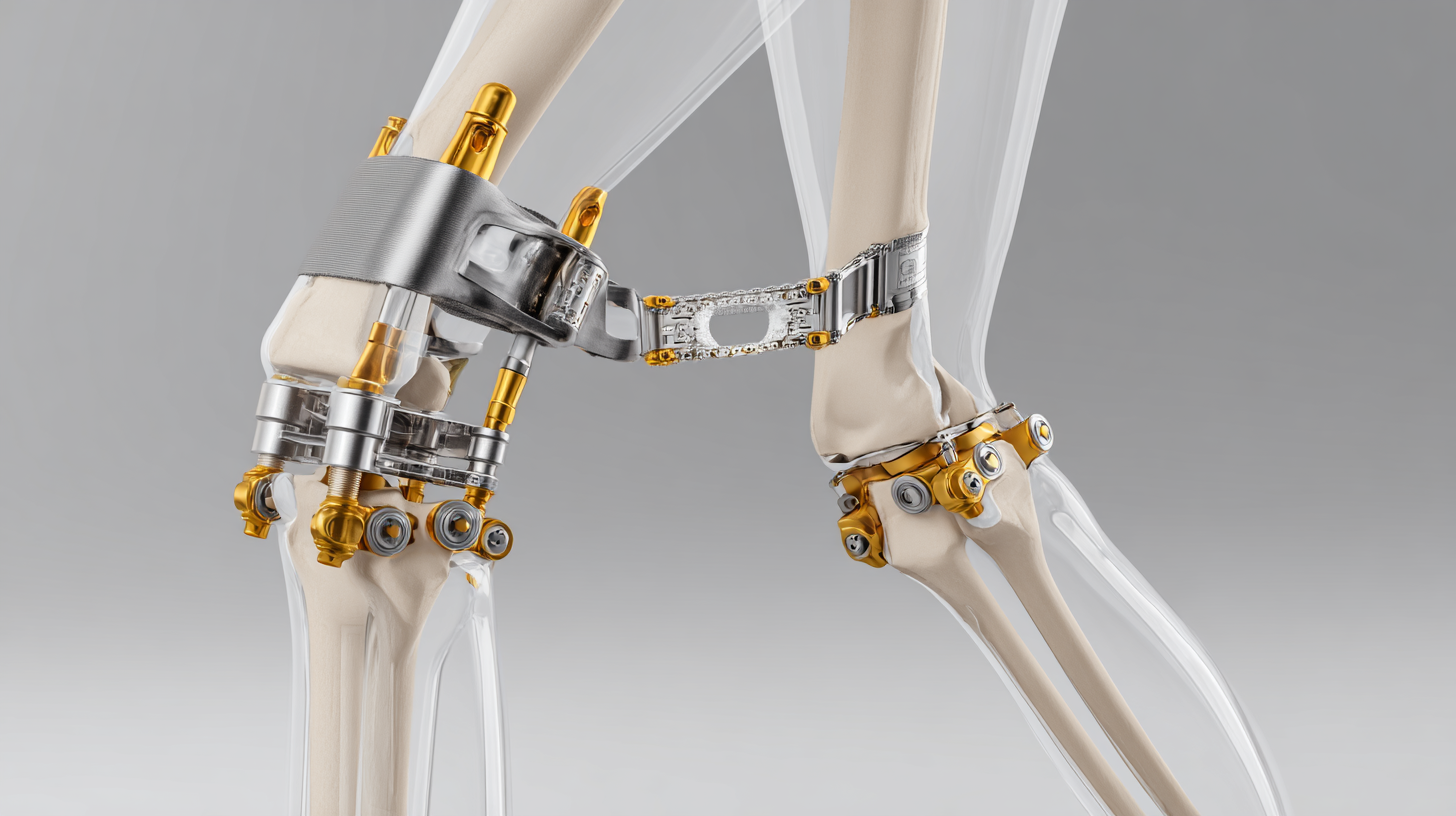

The Hip Arthrosis System comprises various components designed to enhance mobility for individuals suffering from osteoarthritis, particularly in the hip joint. This system includes custom-made orthotics that cater to abnormal walking patterns, which can result from joint degeneration. These orthotics not only provide support but can also help correct gait issues, thereby contributing to improved balance and reduced pain during movement.

Furthermore, incorporating supplements that support joint health can be beneficial for individuals aiming to maintain mobility. Together, these components create a comprehensive approach to managing hip arthrosis, focusing on both alleviating symptoms and enhancing overall functional capacity.